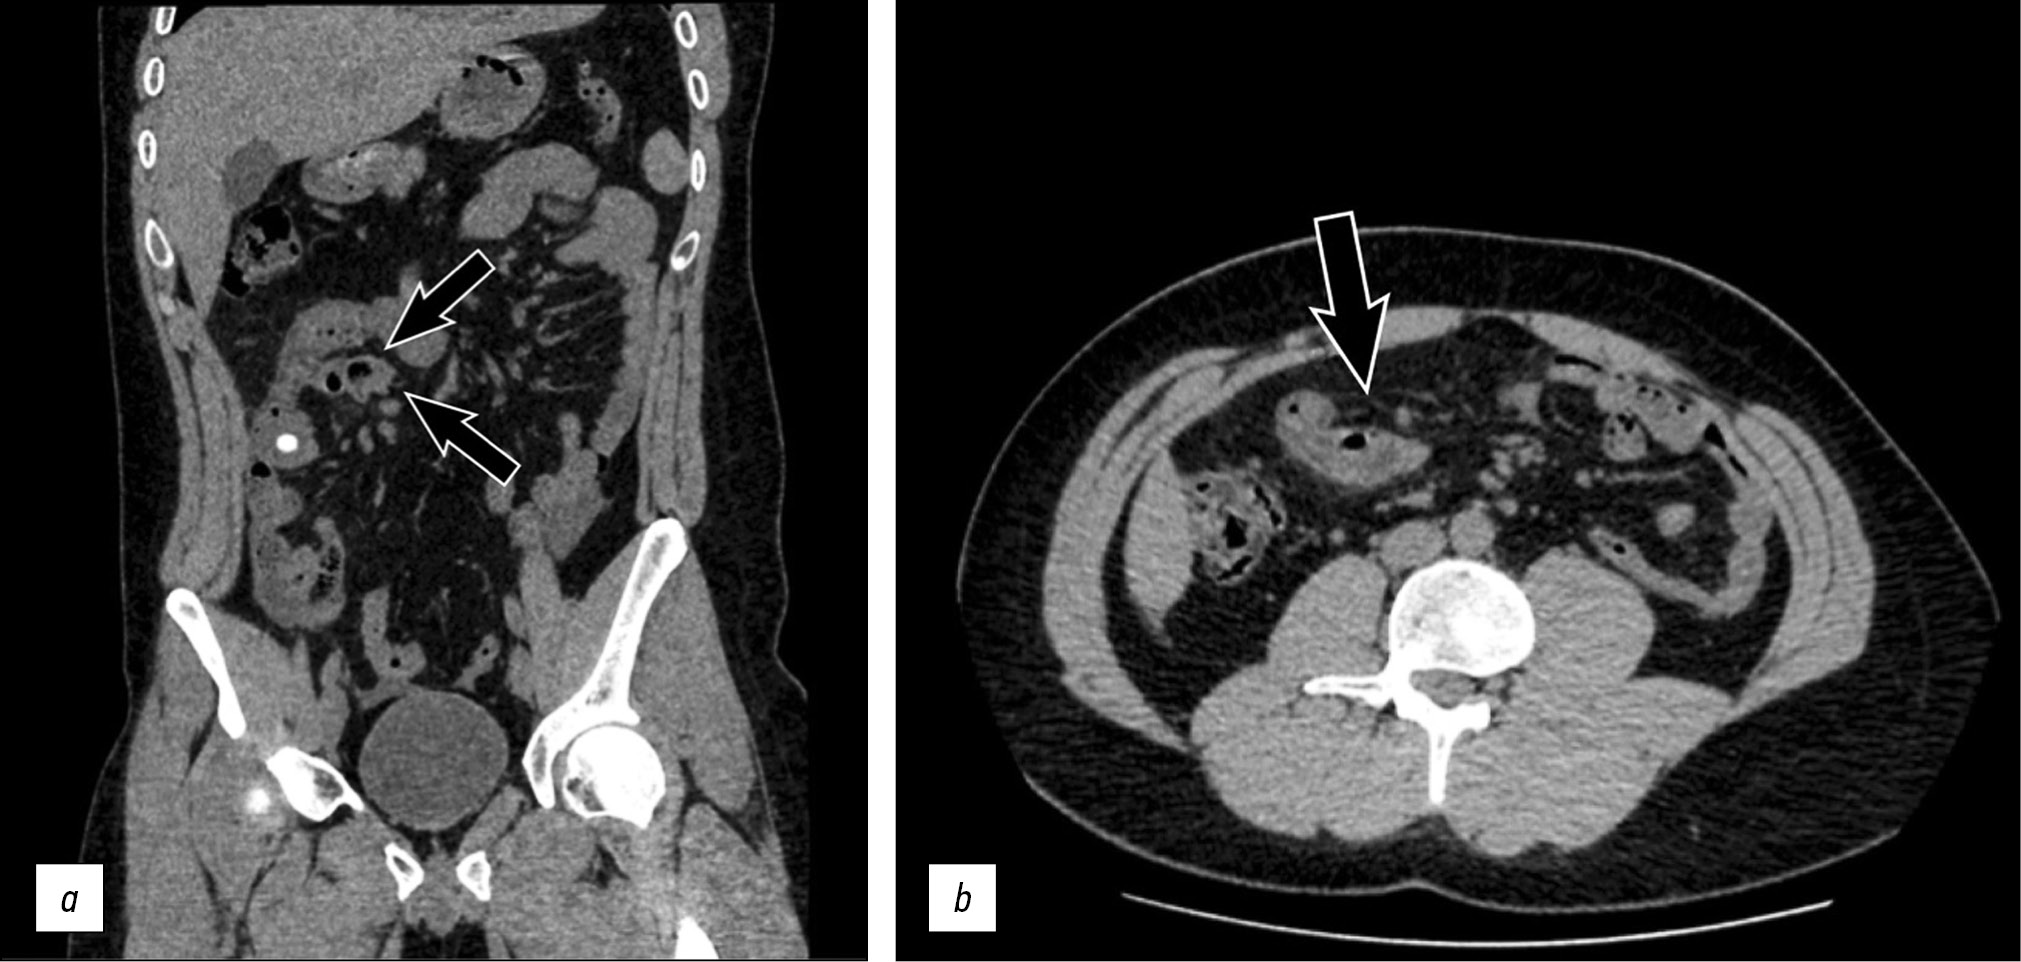

On pre-contrast CT evaluation, a blind-ended intestinal loop in the right quadrants of the abdomen was identified, which was associated with diffuse mesenteric edema and multiple contiguous lymphadenopathies (Fig. 1a, b); a post-contrast CT was performed a few hours later, which showed an intense contrast enhancement of the intestinal wall at the level of the blind-ended loop.

Fig. 1. This coronal (a) and axial (b) pre-contrast computed tomography images showing a blind-ended intestinal loop (arrows) in the right quadrants of the abdomen with associated mesenteric edema and multiple contiguous lymphadenopathies.